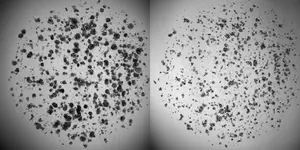

He has created a catalogue of cancer cells from over a hundred patients. The cancer cells have been donated for research and were collected from tumours that have been surgically removed. First, the tumours were cut up into tiny pieces, and then the different pieces were tested with various types and doses of chemotherapy.